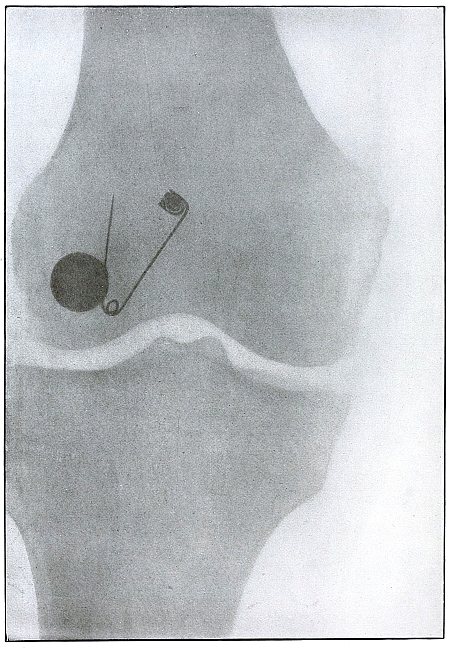

Rifle—Plate 65.

Gunshot Fracture of the Tibia.

The course of the bullet was transverse, from within outward, striking the bone near the outer border with the velocity of mid or long range, producing long fissures without separation of fragments.

The safety pin, of course, lies in the dressings and on the side away from the plate, as shown by its somewhat indefinite outline and increased length.

The wounds of entrance and exit are practically the same.

The treatment in such cases is that of a simple fracture, except for the management of an occasional infection, and the results are favorable. [Pg 142]